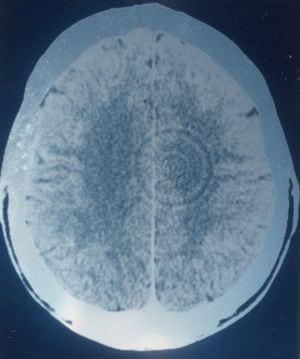

Laut Hamer sollen im Rahmen eines so genannten DHS innerhalb von Bruchteilen einer Sekunde im Hirn nicht näher erläuterte Veränderungen ablaufen, die sofort radiologisch in einem CT erkennbar wären und sich durch eine als Schießscheibenmuster bezeichnete Abfolge regelmäßiger exakter konzentrischer Kreise um ein angenommenes "Relaiszentrum" erkennbar machten. Die gemeinten ca-HHs sollen nach Hamer im Laufe der Zeit wachsen, sich also weiter ausdehnen. Weiter gibt Hamer an, dass es sich hierbei nicht um plötzliche Dichteänderungen handeln soll. Eine Entstehung von radiologisch erfassbaren Dichteänderungen in Sekundenbruchteilen ist darüberhinaus unmöglich. Da sich Kontraste im CT-Bild jedoch ausschließlich aufgrund von Dichteänderungen (in Hounsfield-Einheiten) im Gewebe ergebem, widerspricht sich hier die Hamer'sche Lehre selbst.

Die von Hamer präsentierten "Schießscheibenmuster" sind eindeutig technisch bedingte Ringartefakte (engl.: ring artifact oder ring artefact), die Gegenstand der Radiologenausbildung und aufgrund ihrer Eigenschaften problemlos als solche erkennbar sind. So zeichnen sich derartige Ringartefakte durch eine mathematisch exakte Reihenfolge hypo- und hyperdenser Ringformationen aus, die vorhandene anatomische oder pathologische Strukturen überlagern und auf mehreren Schichten gleichförmig erscheinen. Eine Verlagerung vorhandener anatomischer Strukturen findet nicht statt, Hirnventrikel oder knöcherne Strukturen werden überlagert, was für pathologische Strukturen oder allgemein biologische Strukturen auszuschließen ist.

Ringartefakte lassen sich gut aus der Kenntnis des Aufbaus eines CT-Scanners erklären und treten auf, wenn es entweder zu einem Defekt an einem der zahlreichen Sensoren kommt oder zu Beginn der Computertomografie die Kalibrierung unterlassen wird. CT-Scanner müssen zyklisch kalibriert werden, manche ältere Typen beispielsweise mehrmals am Tag. Durch gezieltes Unterlassen einer Kalibrierung lassen sich auf Wunsch beliebige Ringartfakte künstlich erzeugen und bei entsprechender Lagerung des Patienten auch an jeder gewünschten Stelle im CT. Der mathematische Mittelpunkt der Ringstruktur stimmt dabei mit der Drehachse des Scanners überein, diese wird bei der Untersuchung durch einen Lichtstrahl auf die Haut des Patienten angezeigt.

| Seite 209: eindeutiger Ringartefakt mit mindestens 7 konzentrischen Ringen, die sich über beide Hemisphären erstrecken ohne Gewebe zu verlagern. Die gezeigten Ringe dringen in die seitliche Wand der Kalotte ein und treten aus ihr wieder aus. Die gezeigten Artefakte können unmöglich biologischer Herkunft sein. Hamer sieht hier einen HH in ca-Phase. |

Seite 210: Ein weiterer eindeutiger und imposanter Ringartefakt mit mindestens 10 perfekt konzentrischen Ringen, die sich über beide Gehirnhälften erstrecken ohne bekannte anatomische Strukturen (wie Hirnventrikel) zu verlagern. Die Ringe treten aus der Kalotte ein und wieder aus. Hamer sieht hier einen HH nach einem Trennungskonflikt. |

| Seite 211: Ein weiterer Ringartefakt mit mindestens 20 konzentrischen Ringen. Die fissura longitudinalis ist nicht verlagert. Nach Hamer sehen wir die Aufnahme eines römischen Patienten der einen Konflikt erlitten hätte, nachdem er wegen illegaler Bautätigkeit angezeigt worden wäre. |